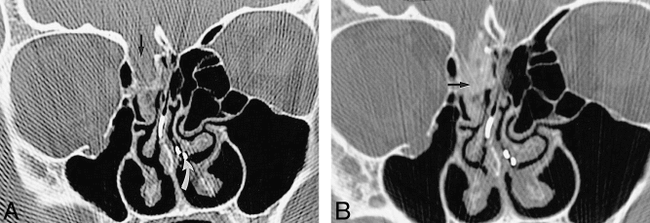

Patient with a bone defect revealed by CT and positive results of radionuclide cisternography and CT cisternography.

A, Coronal CT scan of the face shows a defect (arrow) of the lateral sphenoidal sinus roof with mucosal thickening filling the sphenoidal sinus.

B, Coronal contrast-enhanced CT cisternogram shows contrast medium extending through the defect (arrow) and within the right sphenoidal sinus (curved arrow). The nasal pledgets indicated a leak in the region of the right sphenoethmoidal recess, although the cisternogram did not show abnormal accumulation of the radionuclide. The defect and CSF leak were confirmed at surgery.